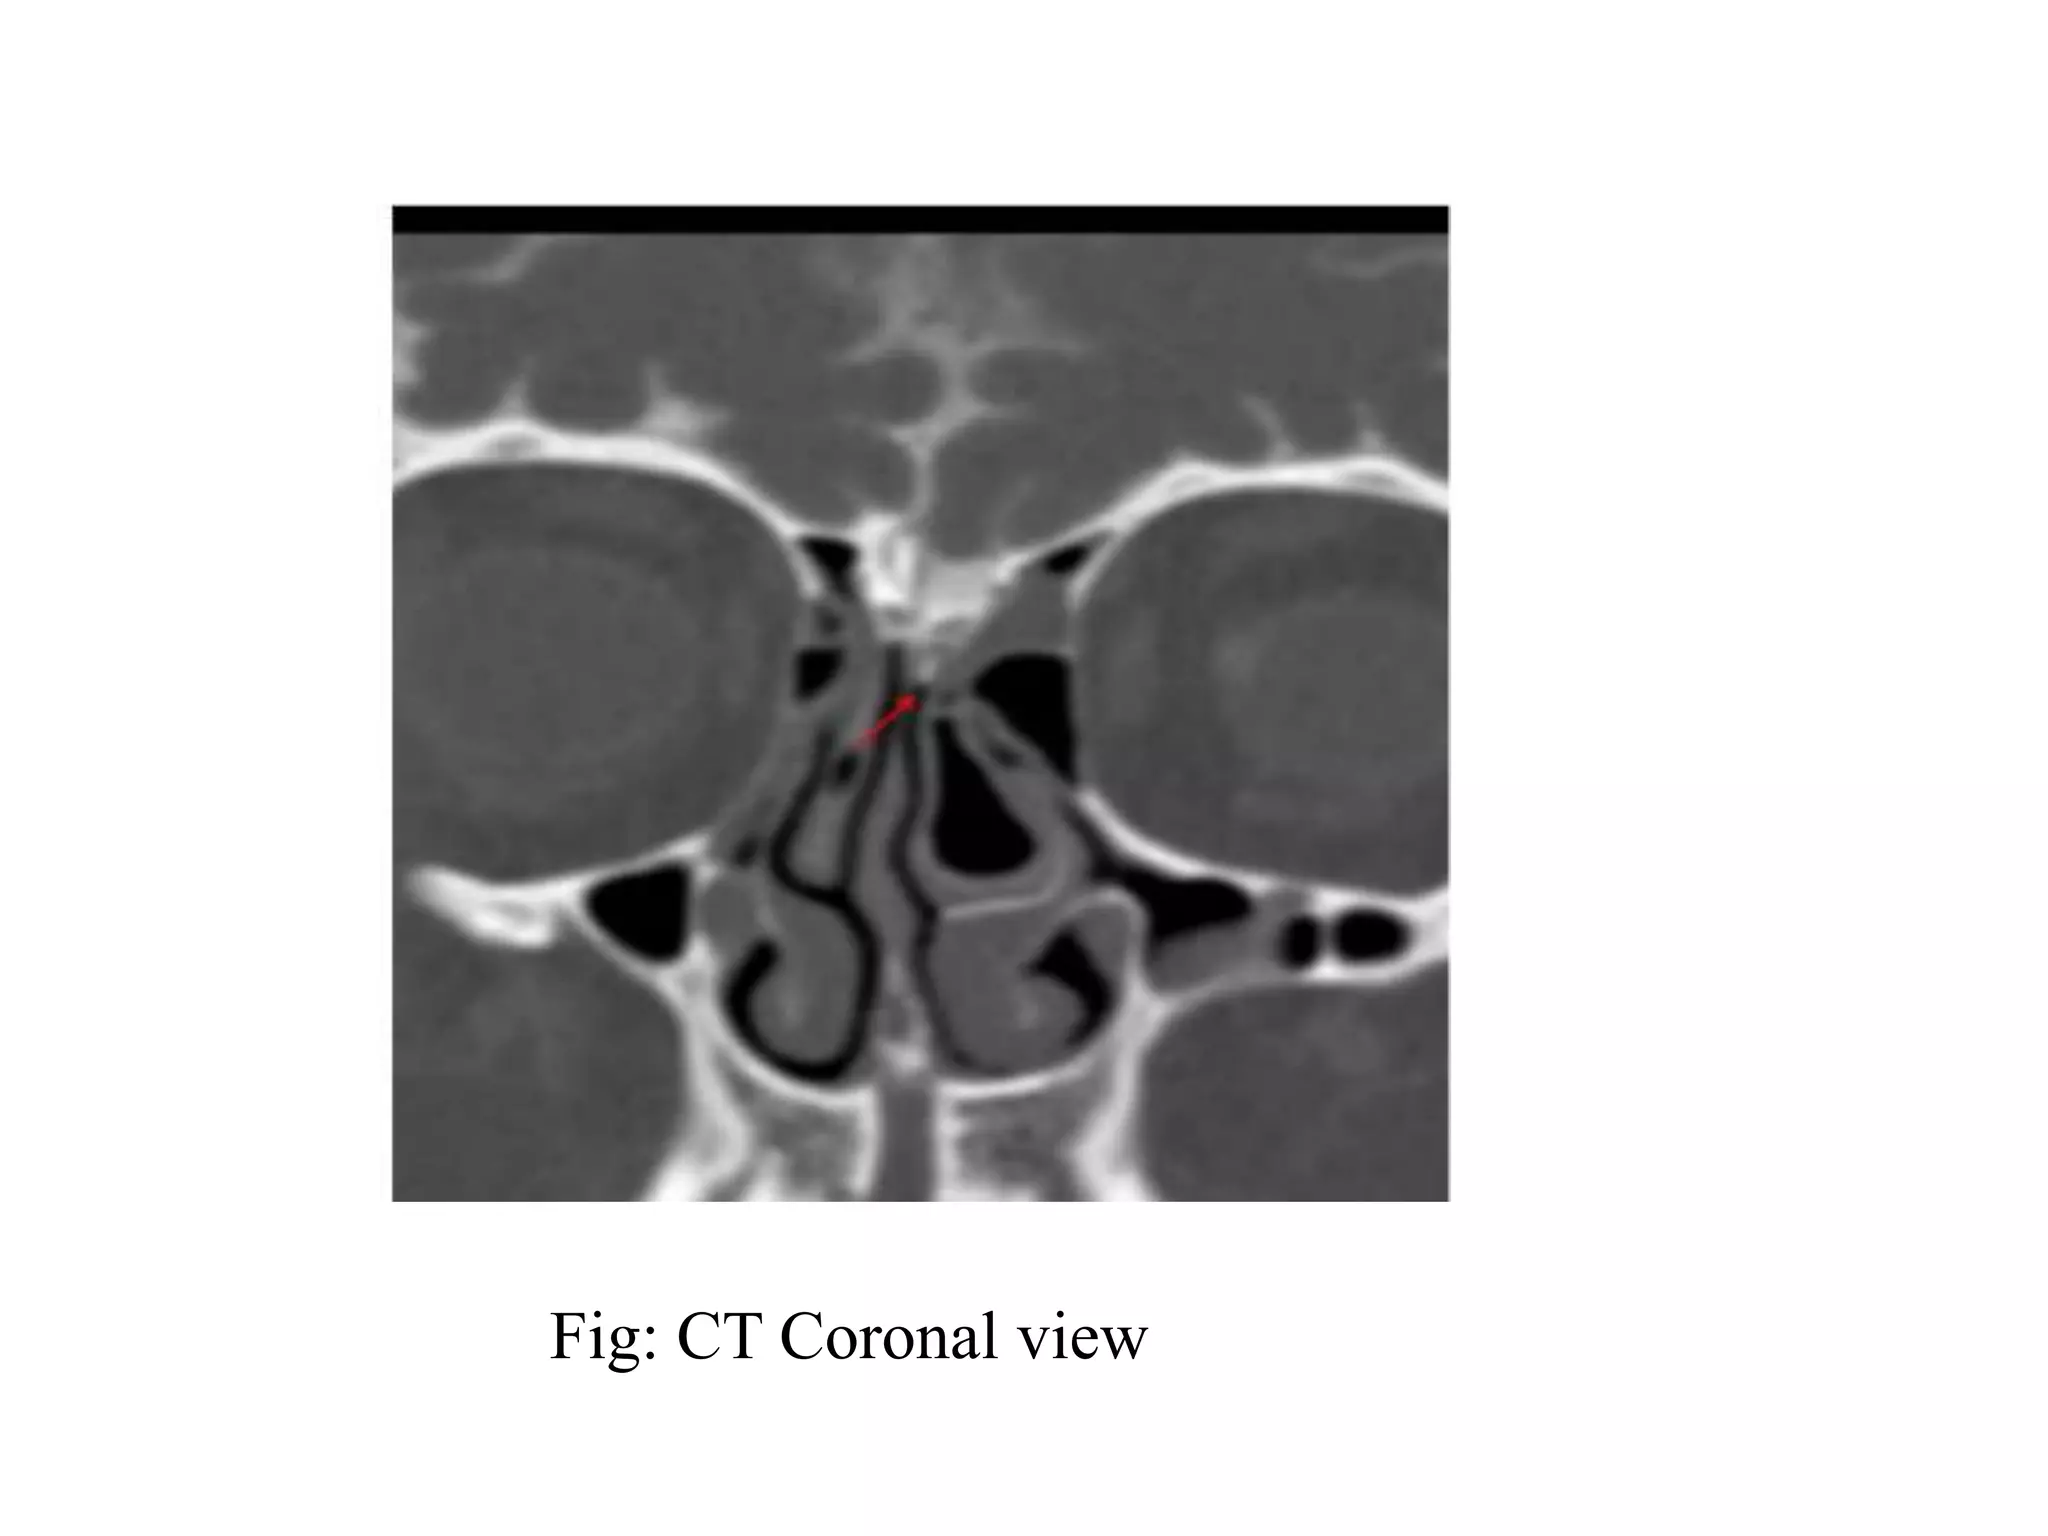

Fig: CT Coronal view

Criteria of image quality

• Symmetric position with the orbital plates

overlapping with each other.

• Absence of the motion artifacts.

• Absence of beam hardening.

• Optimal opacification of the cisterns and the

sulcal spaces.